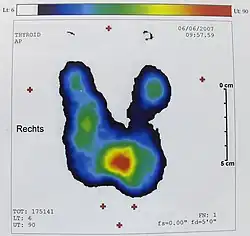

Szintigrafie

Die Schilddrüsenszintigrafie erlaubt die Beurteilung der regionalen und globalen Funktion der Schilddrüse.

Szintigrafie mit Technetium

Der am häufigsten verwendete Tracer ist 99mTc (Natriumpertechnetat, Na99mTcO4). Er steht in allen nuklearmedizinischen Praxen zur Verfügung und hat günstige physikalische Eigenschaften bezüglich Strahlungsart (reiner Gamma-Strahler), Strahlungsenergie (140 keV) und Halbwertszeit (6 Stunden). Der Tracer wird zwar analog zu Jod in die Schilddrüse aufgenommen („Jodination“), aber nicht in Schilddrüsenhormone eingebaut („Jodisation“). Die Aufnahme des Technetiums in die Schilddrüse (Uptake) ist aber proportional zur Aufnahme von Jodid. Die Strahlen-Dosis für die Schilddrüse beim Schilddrüsenszintigramm beträgt etwa 0,12 cGy, die effektive Äquivalentdosis für den ganzen Körper bei einer verwendeten Aktivität von 75 MBq beträgt etwa 0,9 mSv.[5] Technetium wird auch in die Speicheldrüsen und in die Magenschleimhaut aufgenommen.

Der 99mTc-Uptake beträgt normalerweise etwa 0,5 bis 2 % des intravenös verabreichten Technetiums. Ein global erhöhter Uptake findet sich bei Jodmangel, unter Therapie mit Thyreostatika sowie beim Morbus Basedow; ein regional erhöhter Uptake bei autonomen Adenomen. Ein global verminderter Uptake lässt sich nach Jodexposition (zum Beispiel Kontrastmittel oder Amiodaron), unter der Einnahme von Natriumperchlorat oder Schilddrüsenhormonen sowie bei Autoimmunthyreoiditis, Thyreoiditis de Quervain und bei sekundären Hypothyreosen nachweisen. Ein regional verminderter Uptake findet sich bei der Thyreoiditis de Quervain und bei kalten Knoten.

Suppressionsszintigrafie

Zum Nachweis einer Schilddrüsenautonomie, die sich bei normaler Stoffwechsellage szintigrafisch nicht nachweisen lässt, kann die Szintigrafie unter Suppression dienen. Hierzu nimmt der Patient vorübergehend nach vorgegebenem Schema Schilddrüsenhormone ein, die über den thyreotropen Regelkreis zur Verminderung des TSH-Werts führen („Suppression“). Im Szintigramm unter Suppressionsbedingungen nimmt nicht-autonomes Schilddrüsengewebe keinen Tracer auf, so dass sich autonome Areale besser demarkieren. Ein Gesamt-Tc-Uptake in der Schilddrüse über 3 % unter Suppressionsbedingungen weist auf ein hohes Risiko zur Entwicklung einer Hyperthyreose nach Jodexposition hin.